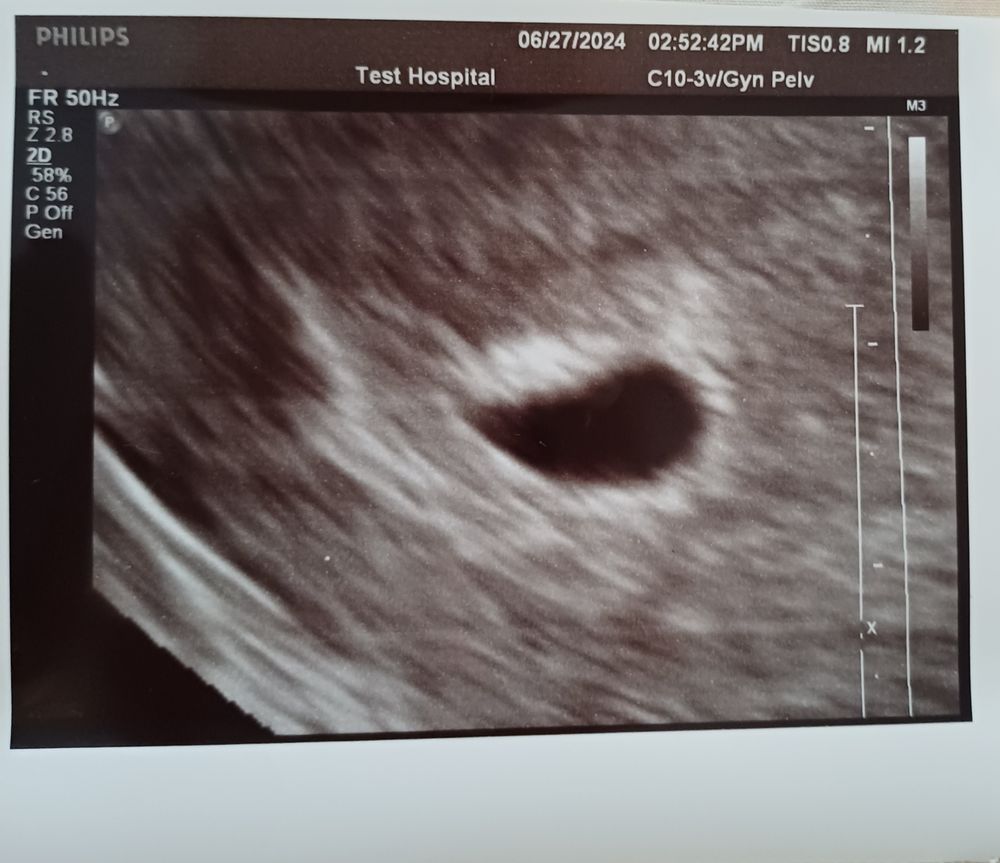

5 неделя беременности, (последние месячные были 12 мая )была на 2 узи ПЯ 12-9 мм эмбриона не видно, моя доктор говорит шансов очень мало и нужно убирать всю поддержку, ей и ПЯ не особо понравилось говорит должно было быть побольше.